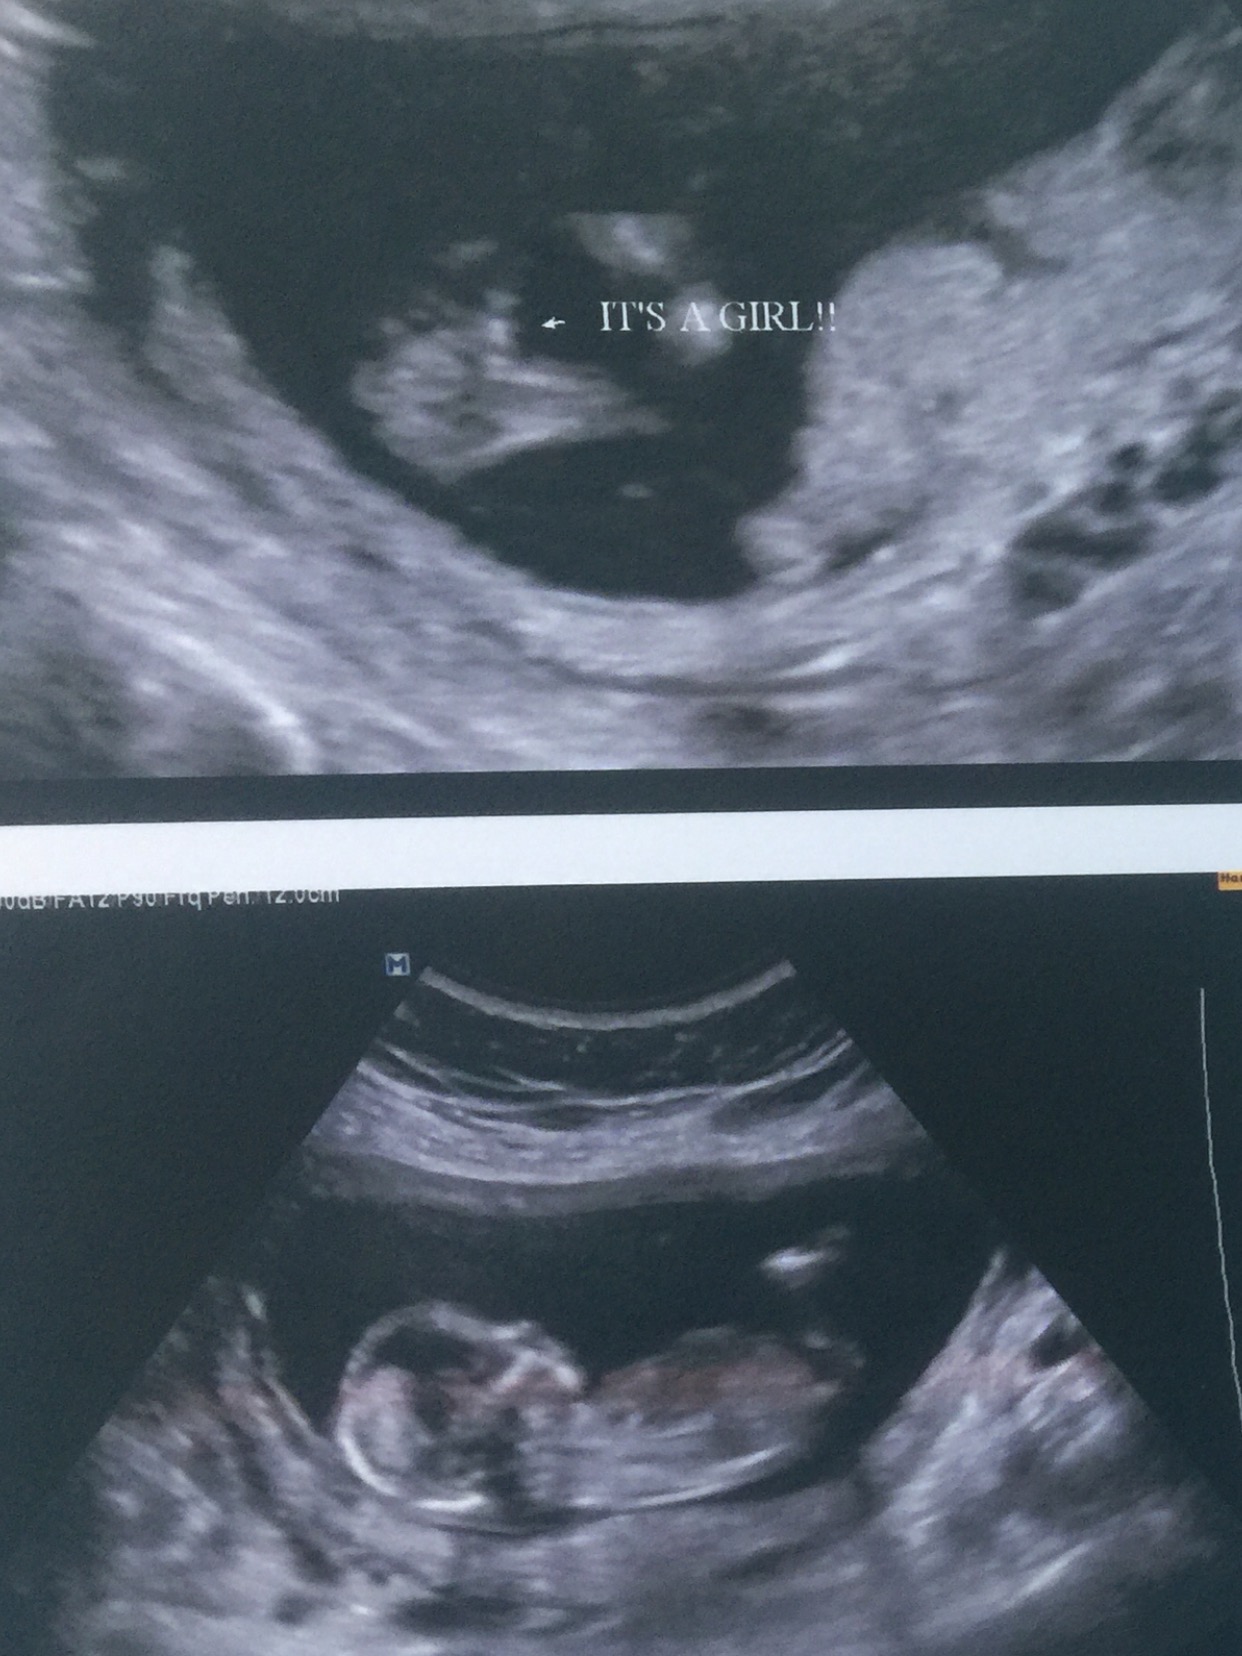

But I have had two scans, and told girl twice. Once the tech was extremely confident and said she wouldnt have said anything at all if she wasnt sure. The second tech said she was pretty sure she saw labia but our little one didnt want open her legs much at all that scan. I have pics from both scans that I want to post that include potty shots and nubs. Input?

Attachment 28271Attachment 28272Attachment 28273Attachment 28274